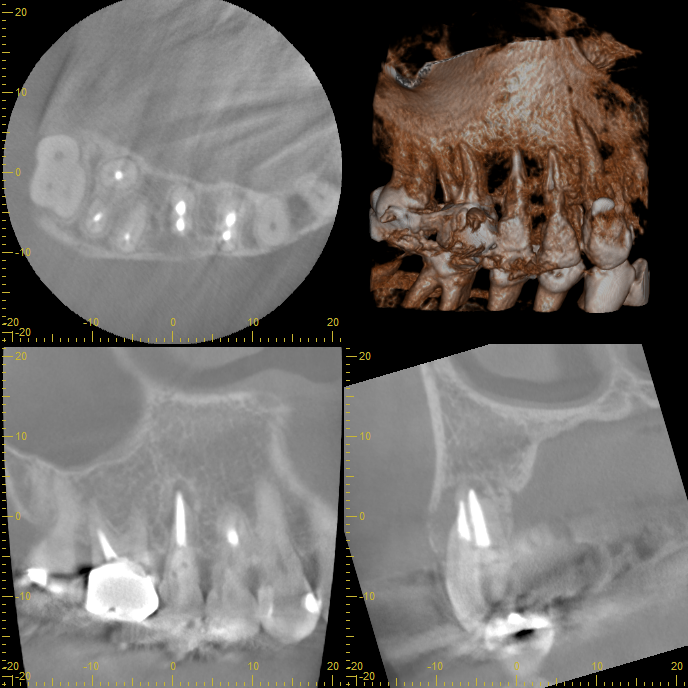

精密なCT診断とシミュレーション

この患者さんの場合、幸いなことに骨欠損がそれほど大きくなかったため、

抜歯即時インプラントの適応となりました。

治療を始める前に、最新のCT撮影を行い、コンピューター上で綿密なシミュレーションを

実施しました。骨の厚み、高さ、密度、神経や血管の位置など、

あらゆるデータを三次元的に分析します。このシミュレーションにより、

インプラントを埋入する最適な位置、角度、深さを1ミリ単位で計画することができるのです。

CTでシュミレーション